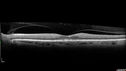

70 year old female diagnosed with diabetes 2 years ago. Her blood pressure was normal at 116/73. She has vision loss for 6 months in both eyes. VA is 20/100 OU. OCT-A shows macular ischemia.

Diabetic Macular Ischemia - Enlarged FAZ - OCT-A426 views70 year old female diagnosed with diabetes 2 years ago. Her blood pressure was normal at 116/73. She has vision loss for 6 months in both eyes. VA is 20/100 OU. OCT-A shows macular ischemia.00000